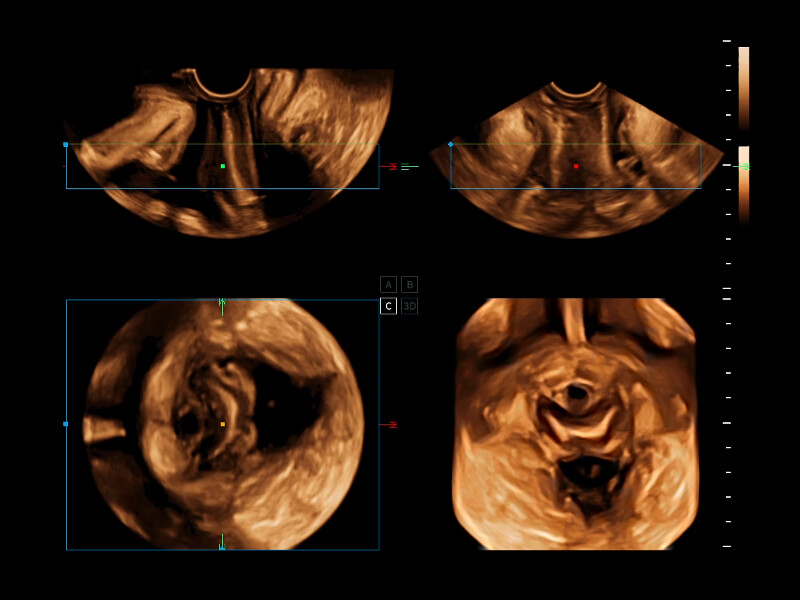

夢(mèng)溪?P80以“關(guān)愛女性”為基石,提供全方位的解決方案,量身定制以滿足女性的健康需求,涵蓋婦科、生殖健康檢查、產(chǎn)前篩查及產(chǎn)后康復(fù)等領(lǐng)域。